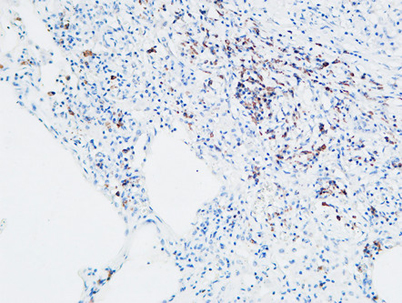

MPO rabbit pAb

Product name: MPO rabbit pAb

Reactivity: Human;Mouse;Rat

Alternative Names: MPO; Myeloperoxidase; MPO

Dilutions: IHC-p: 100-300.Western Blot: 1/500 - 1/2000. ELISA: 1/20000. Not yet tested in other applications.

Immunogen: The antiserum was produced against synthesized peptide derived from the N-terminal region of human MPO. AA range:41-90

Cellular localization: Lysosome.

Background: Myeloperoxidase (MPO) is a heme protein synthesized during myeloid differentiation that constitutes the major component of neutrophil azurophilic granules. Produced as a single chain precursor, myeloperoxidase is subsequently cleaved into a light and heavy chain. The mature myeloperoxidase is a tetramer composed of 2 light chains and 2 heavy chains. This enzyme produces hypohalous acids central to the microbicidal activity of neutrophils. [provided by RefSeq, Nov 2014],